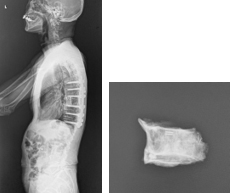

椎体形成術(VP、BKP、VBS)および後方・後側方固定術

椎体形成術でセメントや人工骨を注入して、骨折を人工的に接合します。椎体形成術のみでは固定性が弱い場合や骨脆弱性が強い場合には、スクリューなどを用いて脊椎を安定化させます。原則、手術翌日より軟性もしくは硬性のコルセットを装着し、起立・歩行を開始します。

(左)第12胸椎および第1腰椎の骨粗鬆症性椎体骨折を認めます。(中)MRIでは第1腰椎に大きな骨欠損を認め、骨折が難治性で不安定であることを示しています。(右)第1腰椎に椎体形成術を施行し、さらに骨が脆かったため、頭尾側にスクリューを挿入して固定しています。